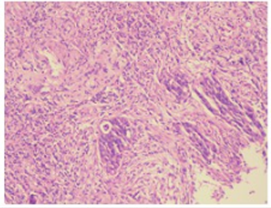

△2019-03-18升结肠病理检测